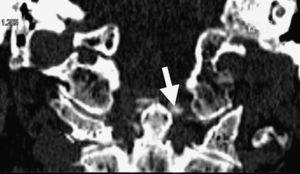

En los estudios radiológicos realizados destaca la aparición de una espondiloartrosis cervical y calcificaciones en el ligamento transverso del atlas y ligamentos alares a nivel de la articulación atlo-axoidea (fig. 4).

El síndrome de Crowned Dens fue descrito por primera vez en 1985 por Bouvet et al1,2. El diagnóstico se basa en la asociación de un cuadro clínico compatible y unos hallazgos en las pruebas de imagen, fundamentalmente depósitos cálcicos en ligamentos de la articulación atlo-axoidea, visibles en la TC3,4.